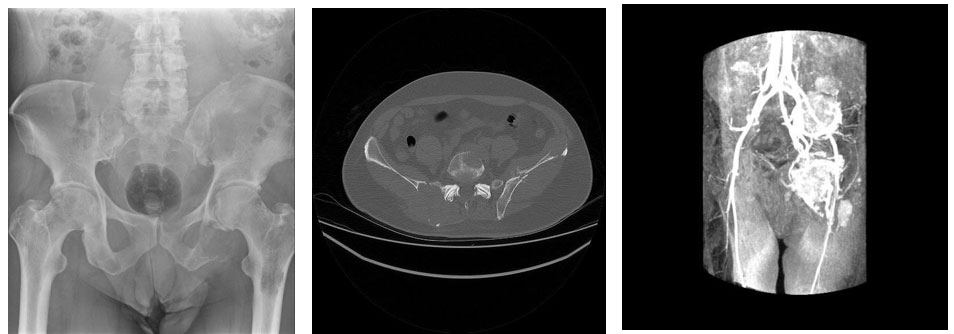

Görsel Açıklamaları

Ameliyat öncesi: Pelvis röntgeninde bir çok metastaz odağı, Tomografide ciddi harabiyet ve kırık, Anjiografide metastaz odaklarında yoğun kanlanma görülmekte